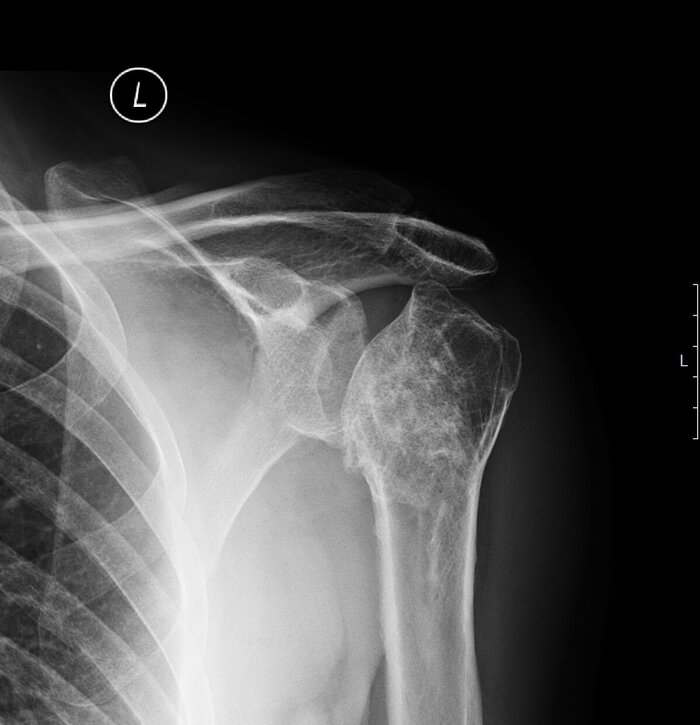

На первом месте рентгенография, где мы видим неравномерное сужение щели, костные разрастания (остеофиты), кисты, субхондральный склероз. Рентгеновского снимка, в большинстве случаев, вполне достаточно для диагностирования артроза.

Выраженный артроз плечевого сустава.